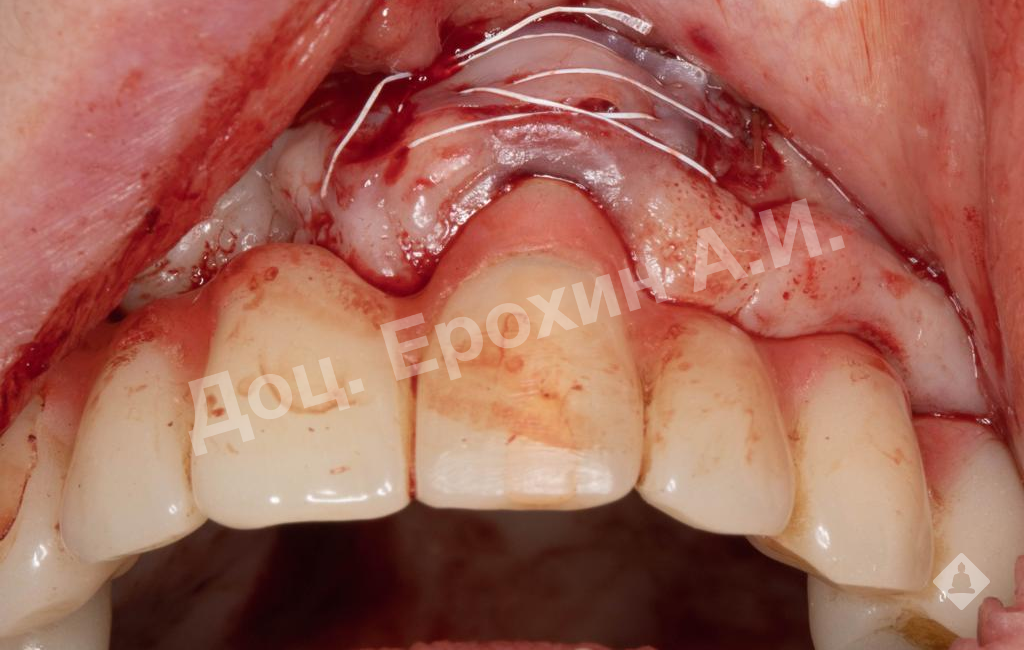

В результате, спустя 10 лет мы видим, что единственная часть десны в области имплантации, не затронутая рецессиями, — это зона, где была проведена трансплантация десневого фрагмента. С целью стабилизации имеющихся имплантатов на повторном приеме была проведена вестибулопластика по Кларку с фиксацией мягкотканных мукотомов, фрагментов эпителия с неба, зафиксированных швами.

В данном клиническом случае мы можем наблюдать эффект так называемого наползающего прикрепления (creeping attachment), когда десна после удаления момента натяжения начинает сама наплывать на ранее оголенные корни зубов и имплантаты.

На фото видно, что в первом сегменте с 2.5-3 мм оголение корня осталось меньше 1 мм, в области имплантата 21 рецессия самоустранилась, а в области имплантата 26 рецессия до операции была 4.5 мм, а после сократилась до 2 мм.